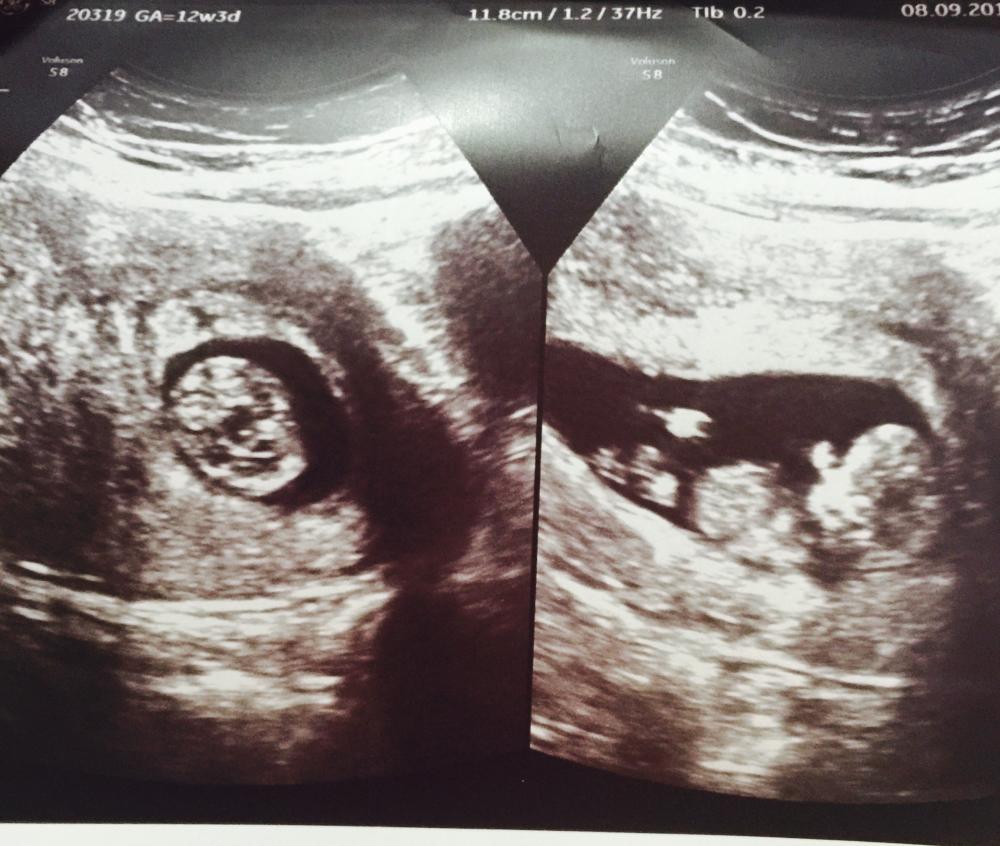

وهو ما يُعرف بنظرية الجمجمة والتي تظهر من خلال السونار في بداية الحمل ؛ حيث تم التوصل العلمي إلى أن شكل جمجمة الجنين الذكر تختلف عن هيئة جمجمة الأنثى ، وقد ظهر في هذه النظرية أن جمجمة الذكور تنزل من الأمام وتنحدر ممتلئة من الخلف ويكون الفك عريضًا ، بينما تأخذ شكل جمجمة الأنثى شكل دائري وتمتلئ من الأمام ويكون الفك مدبب ، ويتم استخدام هذه النظرية في بداية حمل المرأة وقبل أن ينمو الجلد والعضلات على الرأس ، ويُذكر أن هذه النظرية تحقق نسبة نجاح تصل إلى 92%.

يعتمد الأطباء على نظرية النب ثيوري في استطلاع نوع الجنين في الأسابيع الأولى للحمل ؛ وذلك من خلال اتجاه العضو التناسلي للجنين ؛ حيث أن هذا العضو في بداية الحمل لا يمكن معرفة نوعه هل هو لذكر أم لأنثى ؛ لذلك توصل الأطباء إلى معرفة إتجاه هذا العضو والذي يحدد نوع الجنين ؛ بحيث إذا كان العضو مرتفع بزاوية أكثر من 30 درجة فإن الجنين يكون ذكر ؛ بينما إذا نزل العضو لأسفل بزاوية 30 درجة أو أقل فإن المولود يكون أنثى ، وتُعتبر هذه النظرية من أدق النظريات المستخدمة في تحديد نوع الجنين ، وتصل نسبة نجاحها إلى 98%.

اجتهد بعض الأطباء في تطوير الأساليب المستخدمة في هذا الاتجاه ؛ حيث توصل البعض إلى طريقة معرفة الجنين من خلال وضع الحبل السري الذي يرتبط بالجنين وهو ما يُعرف باسم نظرية رامزي نسبةً إلى الدكتور رمزي إسماعيل الذي وضعها ؛ حيث تم اكتشاف أن الحبل السرى يكون على جهة اليسار حينما يكون المولود أنثى ؛ بينما يكون على جهة اليمين في حالة إذا كان المولود ذكر ؛ حيث يتم التعرف على الجنين بهذه الطريقة في الثلث الأول من الحمل ، مع الوضع في الاعتبار أن السونار المهبلي يقوم بتوضيح الصورة بشكل أدق حيث يظهر الحبل السري في الاتجاه الصحيح من خلال هذا السونار ، وتصل نسبة نجاح هذه النظرية في التحقق من نوع الجنين إلى 97%.